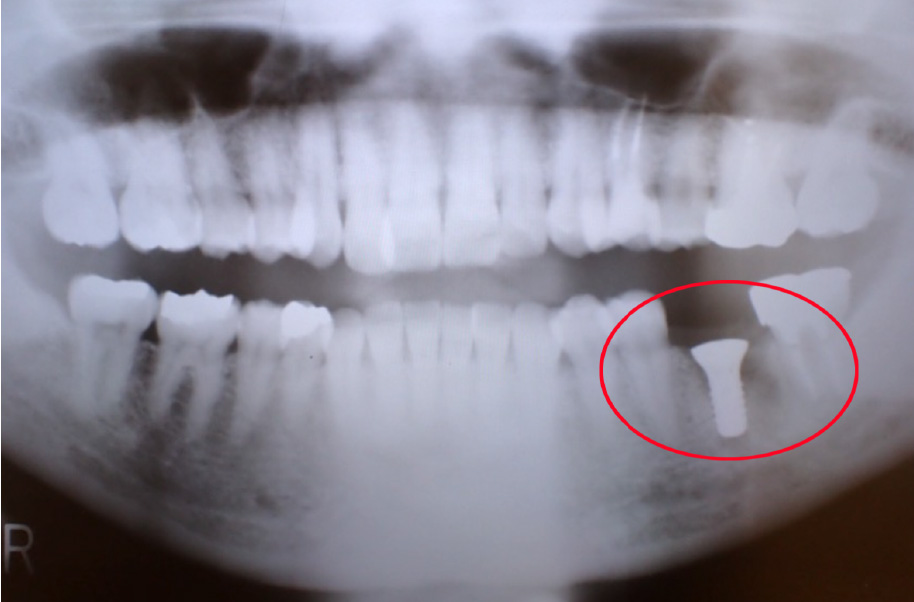

インプラント16年経過症例

80代になっても、ご自身の歯を一本も失わずに噛める喜び

【インプラント埋入直後】

2009年6月当時67歳

2009年6月当時

- 歯を失った右下部分にインプラントを2本埋入し、連結した被せ物(ブリッジ)で噛み合わせを回復しました。

治療から16年が経過し、患者様は83歳になられましたが、インプラントの状態は非常に良好です。

何より素晴らしいのは、「インプラントがしっかりと噛む力を支えてくれたおかげで、 他のご自身の歯への負担が減り、この16年間でさらに歯を失うことがなかった」という点です。

3~4ヶ月ごとの定期的なメンテナンス(パウダーによるクリーニング等)にもしっかりに通っていただいた結果、 現在もしっかりとご自身の歯で食事を楽しんでおられ、全身の健康も素晴らしい状態です。